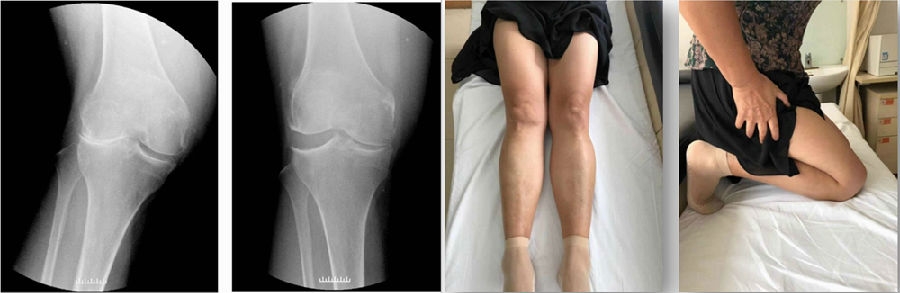

Case1LUK治疗外侧间室OA

术前

术后

Case2:二期Bi-UKA治疗进展性OA

术前影像

术后5年,外侧进展性OA

LUKA治疗外侧进展性OA